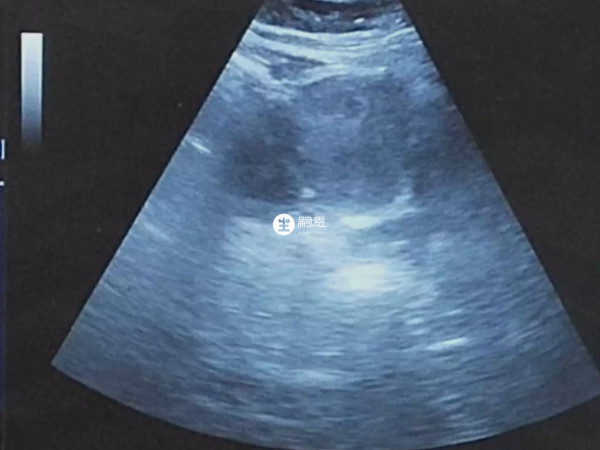

nt檢查是胎兒的頸部透明度檢查,常用於產前篩查,可以早期診斷染色體疾病和早期發現多種原因造成的胎兒異常。nt正常的值是在3mm以內,如果超過3mm,常提示有不良胎兒結果,一般是用B超檢查的。

常規的產科B超檢查主要關注胎兒的發育及大體結構,隨著經陰道超聲的開展和普及,從更深層次關注胎兒各組織結構之間的比例關係,通過定量分析檢測指標來預測胎兒是否存在某種缺陷,尤其染色體異常,如胎兒頸項透明層測定,正在成為產前篩查胎兒染色體異常的有效方法之一。